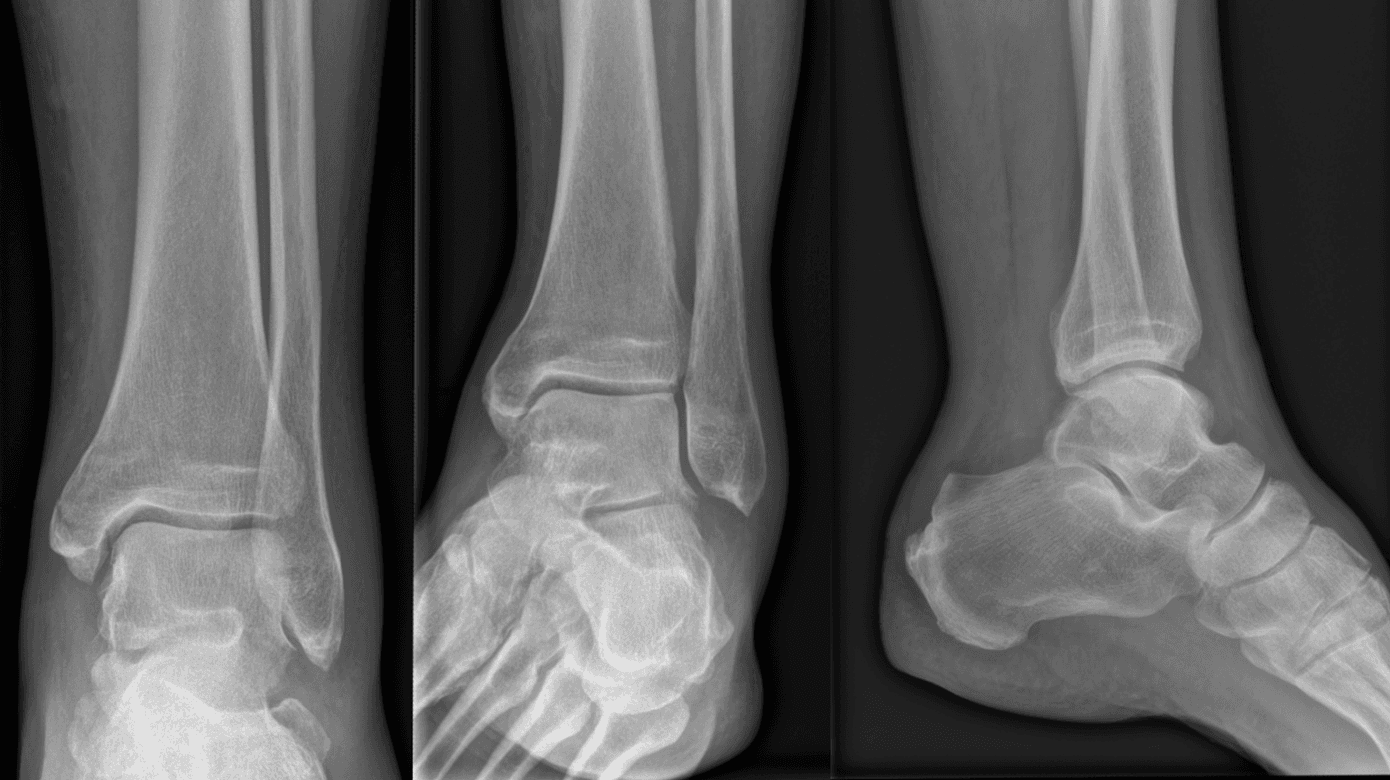

En 59-årig mand mødte i skadestuen med funktionsnedsættelse og smerter i venstre fod. Da han skiftede dæk på bilen, skred hans venstre fod fra hjulnøglen og ramte underlaget. Subjektivt beskrev han et pludseligt smæld i venstre læg. Objektivt observeredes der hævelse, misfarvning og smerter i bagkanten af mediale malleolus, en palpabel defekt i akillessenen samt positiv Matles test og positiv Thompsons test. Anterior-posterior-, mortise- og laterale røntgenoptagelser afslørede en udisloceret, oblik MMF samt sløring og uskarpe konturer af Kagers fedtpude (Figur 1).